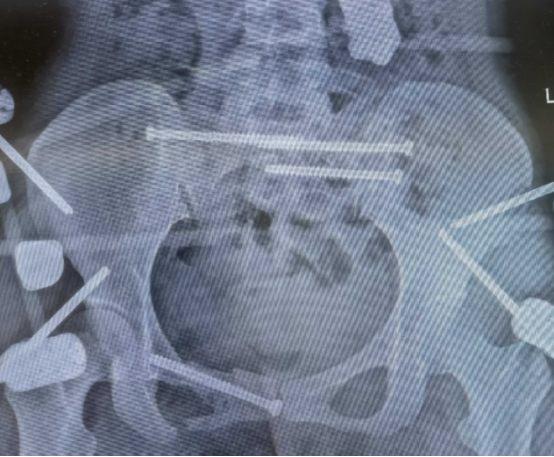

患者的“骶骨骨折”,严重到什么程度?6月19日上午10点半,中心医院东院区的影像检查显示“第1-5骶椎骨折”。

图片

*2025年6月19日患得影像学检查资料

刘华水解释说:“患者受伤后骨盆像风吹样,结构十分不稳定。腰下面的骨头叫骶骨,它是人体结构中重要的骨头,由五块骶椎融合而成,构成骨盆的重要部分。骶骨与骨盆起着传导重力和支持、保护盆腔脏器的作用,有很多的软组织附着。骶骨椎体骨折,必须第一时间手术干预,以避免进一步导致盆腔器官和神经功能损伤。”